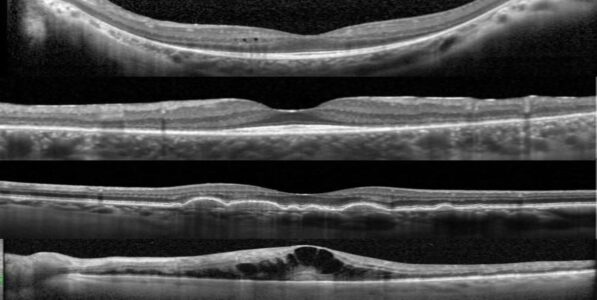

Images en OCT de la région maculaire, objectivant des atteintes des

différentes couches de la rétine : kystes des couches internes de la rétine,

amincissement péri-maculaire des couches externes dans le cadre d’une

maculopathie à l’hydroxychloroquine, drusen, œdème maculaire.

Exemple d’un OCT maculaire et papillaire normaux.